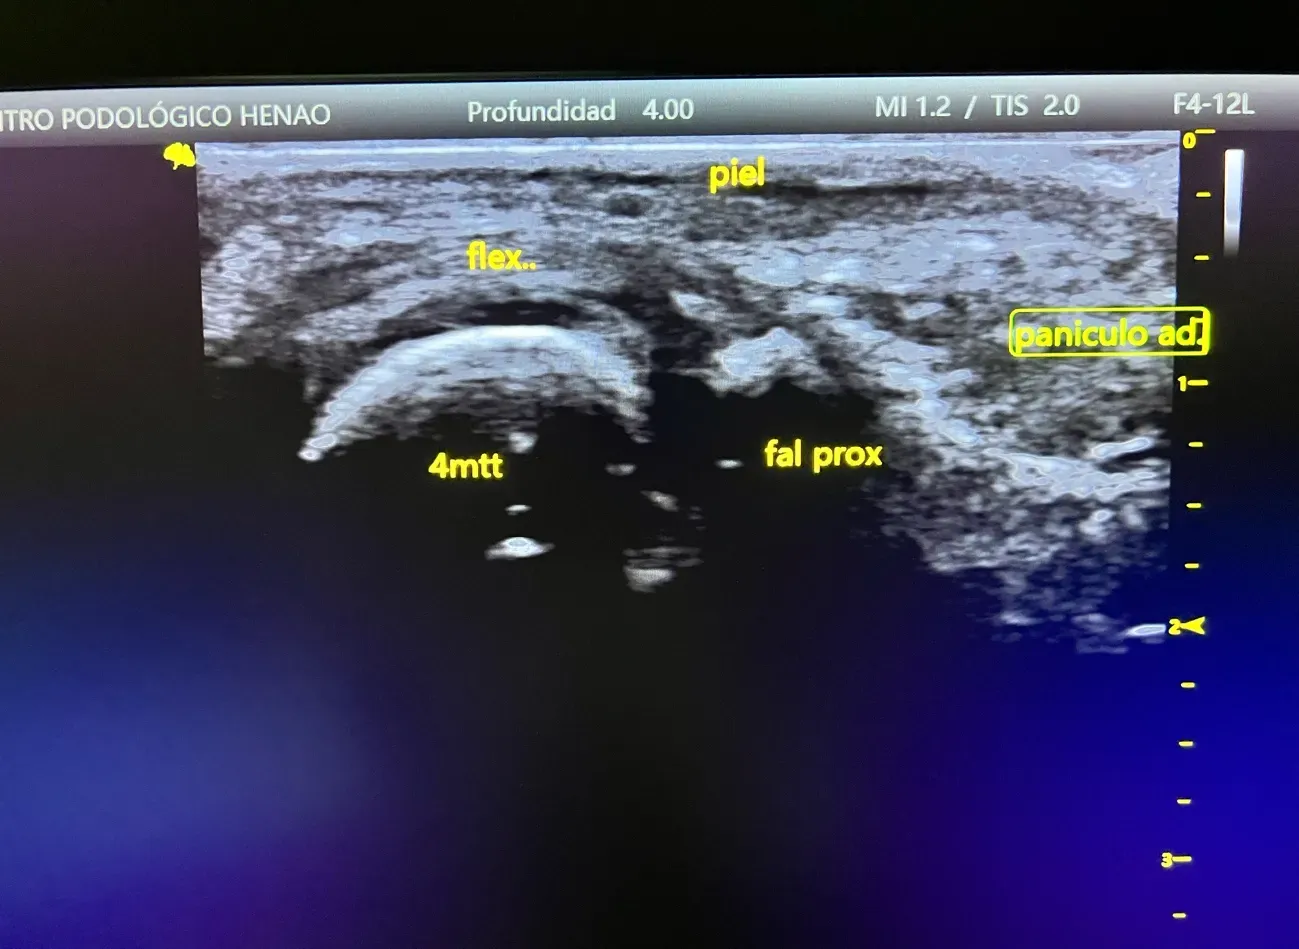

★ Ecografía del PieEstrella

Diagnóstico por ecografía del pie y tobillo sin dolor ni radiación, con resultados inmediatos en consulta.

Metatarsalgia y Dolor en Antepié

El dolor en la parte anterior del pie es muy frecuente en diabéticos. Se debe a alteraciones en el reparto de cargas al caminar, atrofia de la almohadilla grasa plantar y cambios biomecánicos. Puede causar dificultad para caminar y afectar la calidad de vida.

- Atrofia del panículo adiposo plantar: la almohadilla grasa que protege el antepié se reduce